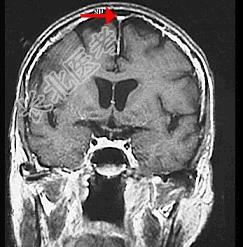

- 单项选择题如图箭头所示,应属于大脑的哪个部位 ( )

A、窦汇

B、横窦

C、直窦

D、上矢状窦

E、下失状窦